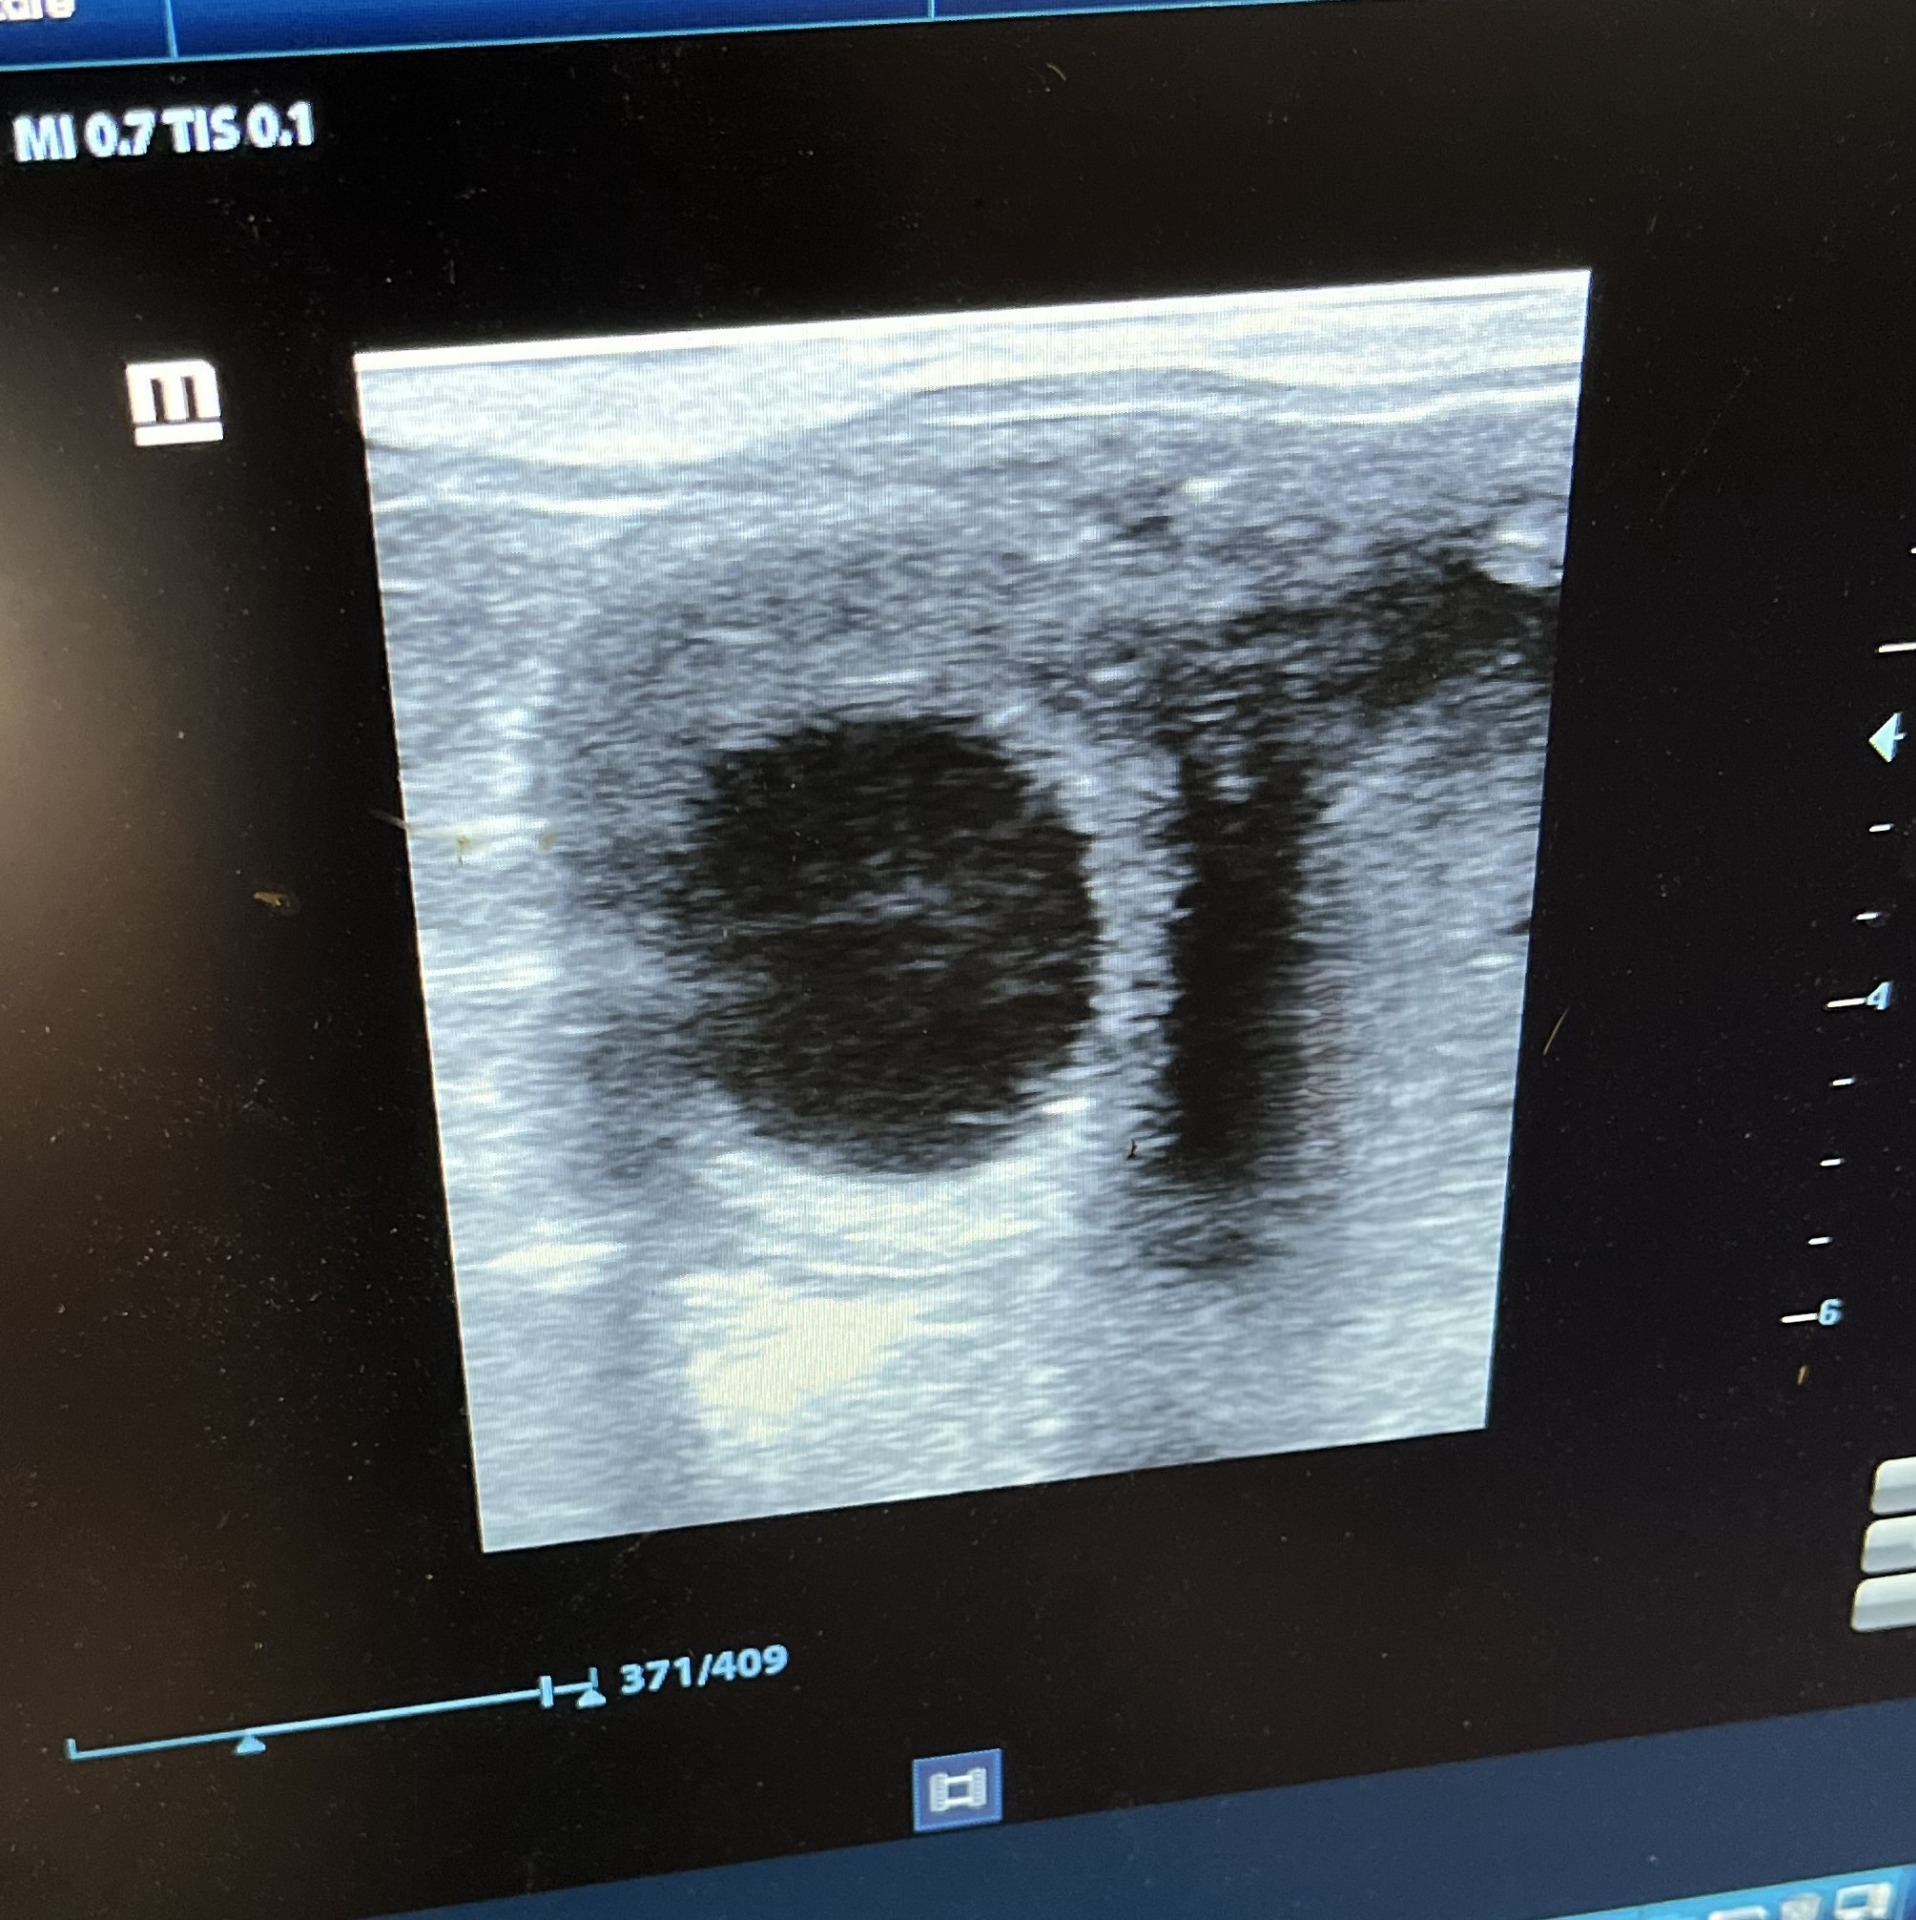

Der tilbydes desuden drægtighedsscanninger og skulle ulykken være ude og din hoppe mister sit foster, så står jeg klar med hjælp.